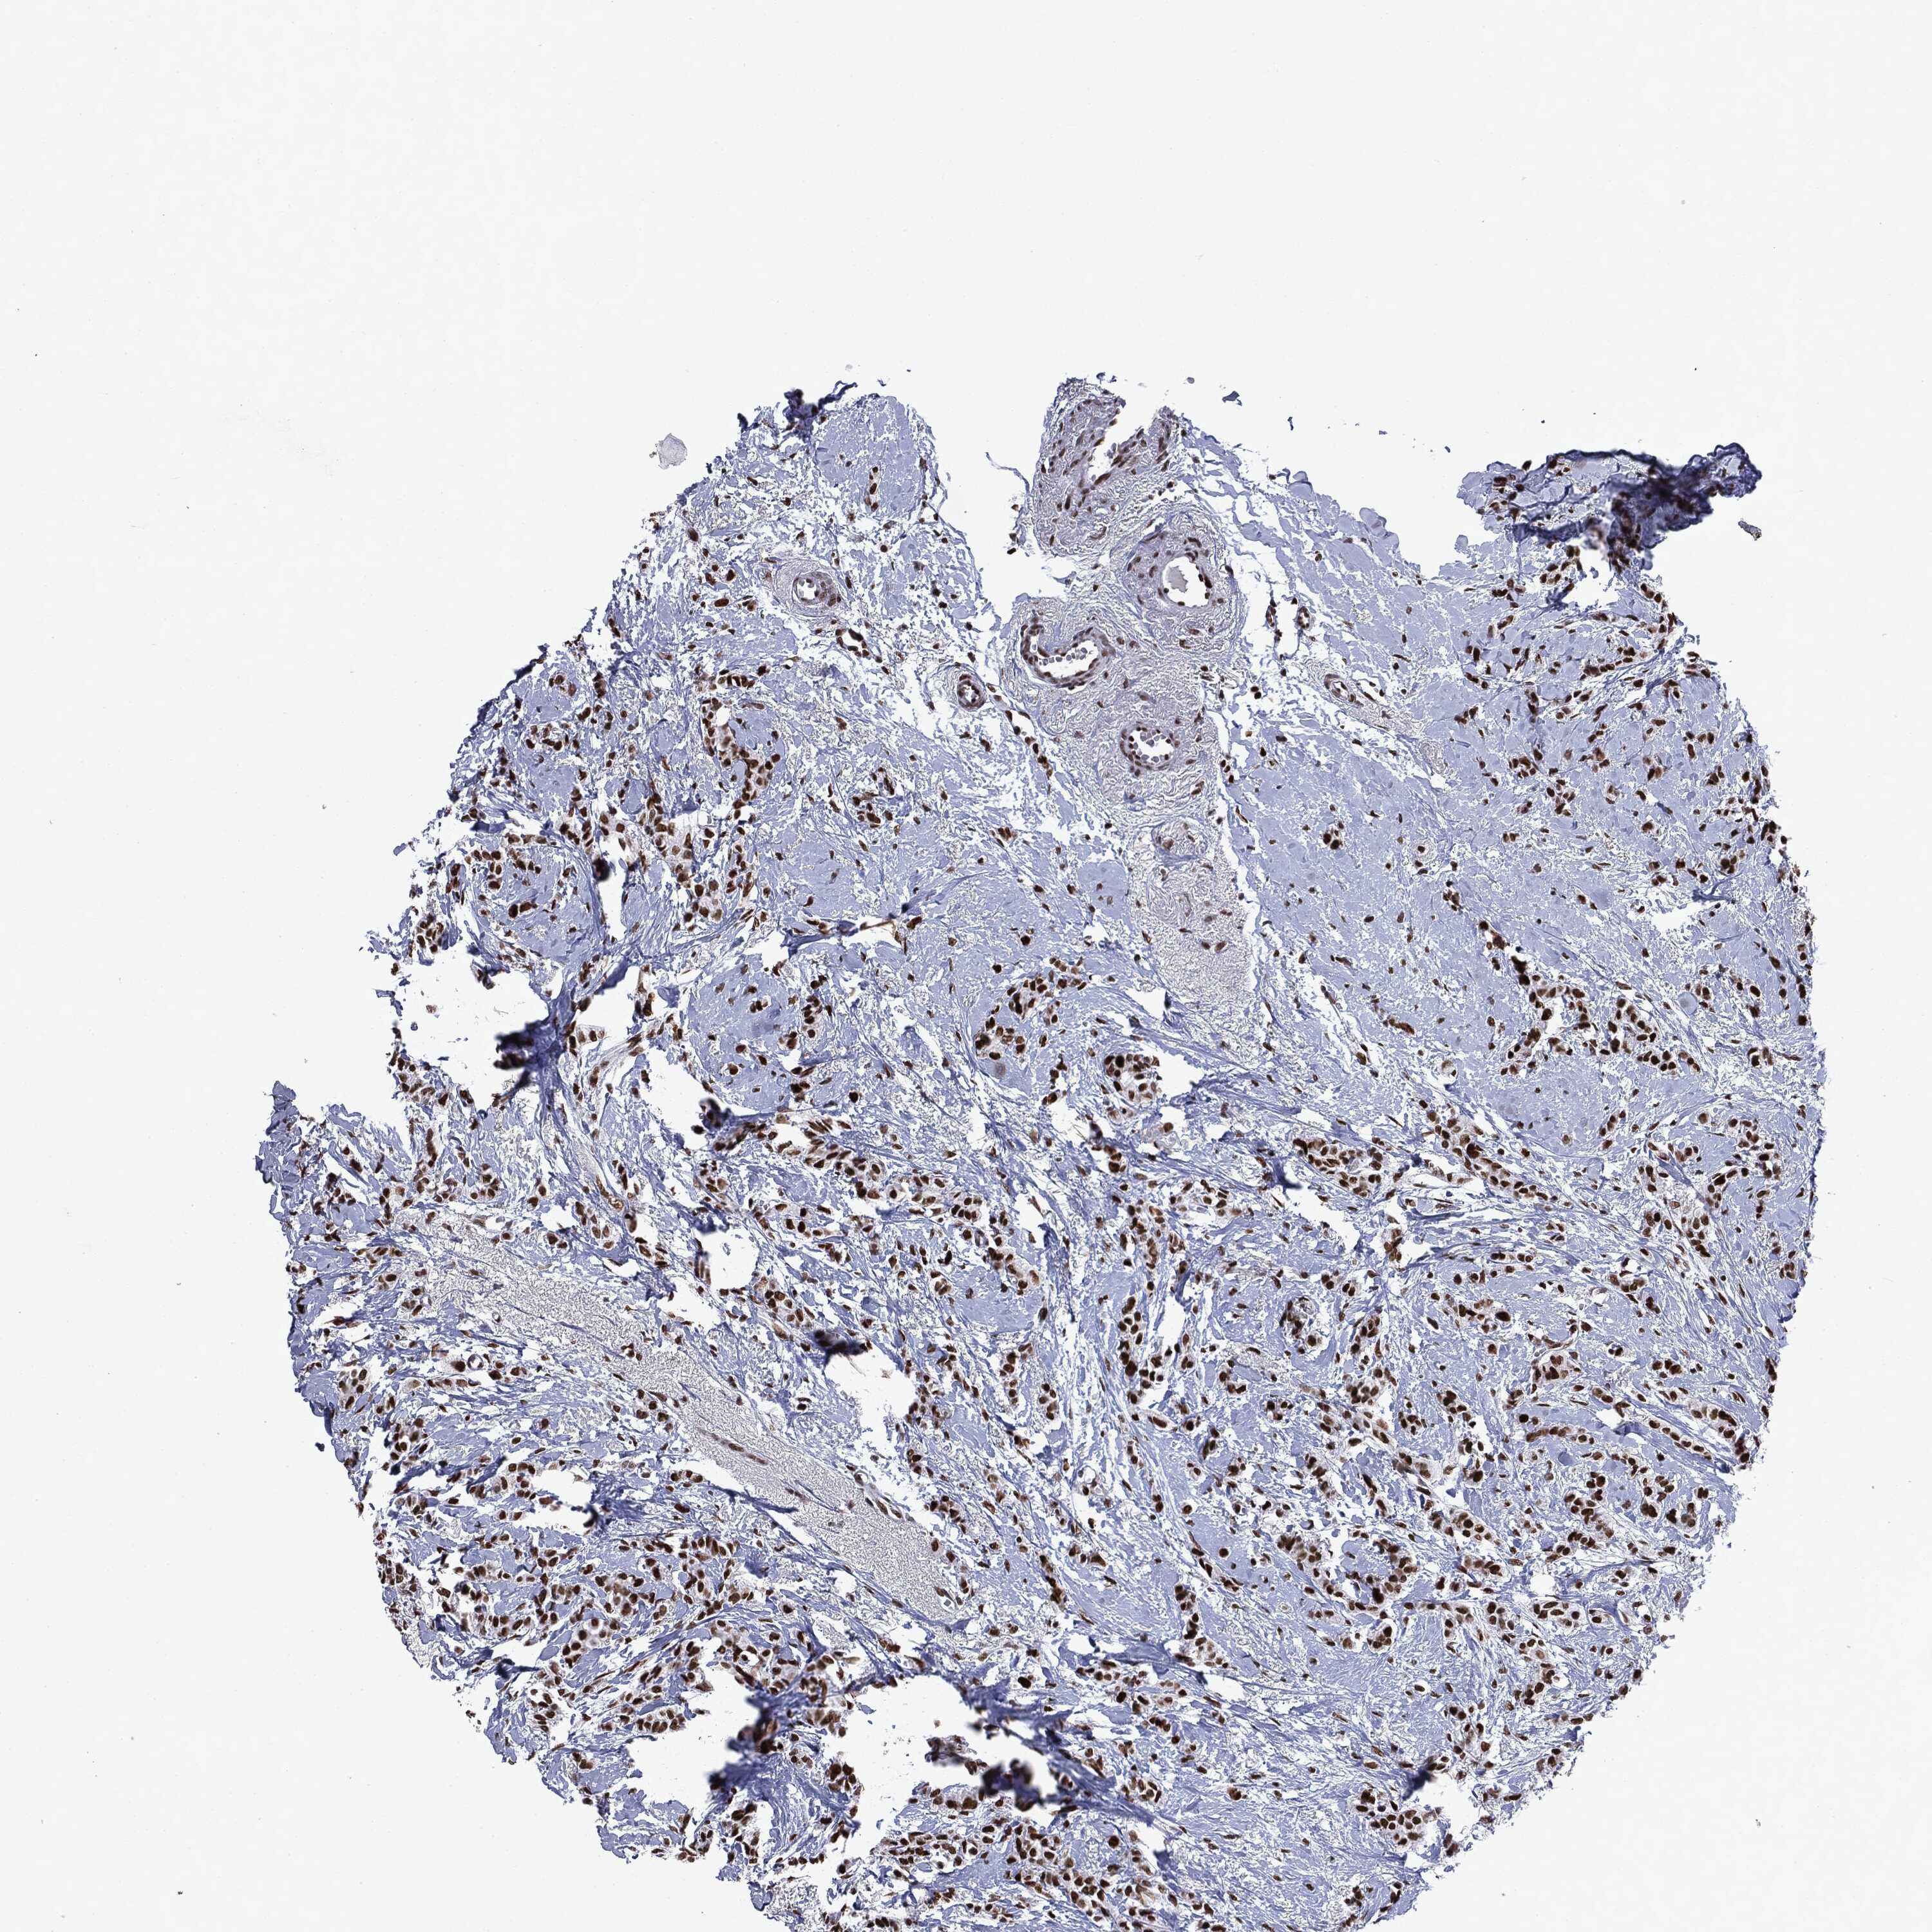

BRCA TCGA BRCA VALIDATION PROTEIN EXPRESSION